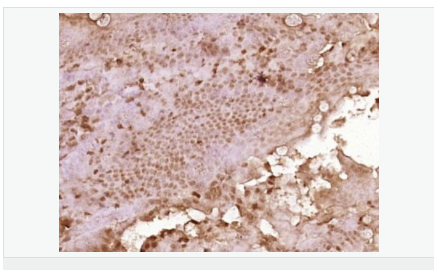

交叉反應(yīng):Mouse,Rat(predicted:Human,Dog,Sheep) 推薦應(yīng)用:WB,IHC-P,IHC-F,ICC,IF,ELISA

產(chǎn)品應(yīng)用WB=1:500-2000 ELISA=1:5000-10000 IHC-P=1:100-500 IHC-F=1:100-500 ICC=1:100-500 IF=1:100-500 (石蠟切片需做抗原修復(fù))

細(xì)胞定位細(xì)胞漿

產(chǎn)品介紹C3orf32 (chromosome 3 open reading frame 32), also known as fls485, is a 353 amino acid protein encoded by a gene that maps to human chromosome 3p26.1. Chromosome 3 is made up of approximately 214 million bases encoding over 1,100 genes. Notably, there is a chemokine receptor gene cluster and a variety of human cancer related loci on chromosome 3. Particular regions of the chromosome 3 short arm are deleted in many types of cancer cells. Key tumor suppressing genes on chromosome 3 encode apoptosis mediator RASSF1, cell migration regulator HYAL1 and angiogenesis suppressor SEMA3B. Marfan Syndrome, porphyria, von Hippel-Lindau syndrome, osteogenesis imperfecta and Charcot-Marie-Tooth disease are a few of the numerous genetic diseases associated with chromosome 3.

Tissue Specificity:

Expressed in enterocytes of small and large intestinal mucosa (at protein level). Expressed in enterocytes, chromaffine and interstitial cells.